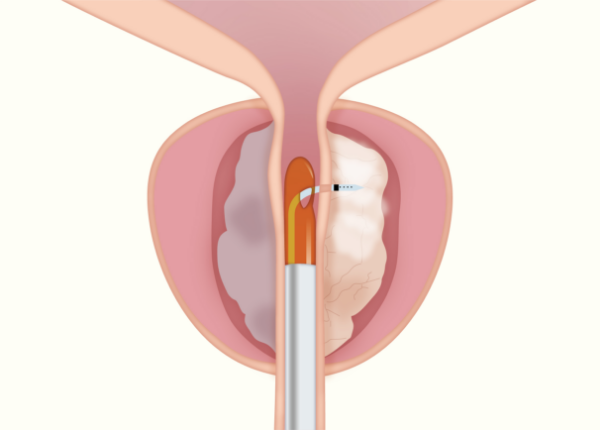

Rezumシステムは、内視鏡を用いて尿道から入り、水蒸気を利用して前立腺肥大症を治療する医療機器です。

肥大した前立腺組織内に103℃の水蒸気を9秒間噴霧し、組織を約70℃まで上昇させることで組織を壊死させます。

従来の前立腺肥大症に対する温熱療法と比べて、水蒸気を利用しているため対流によってムラのない治療効果が発揮され、尿道粘膜や性機能温存が可能です。

治療・手術時間は5〜15分程度で、治療効果は約2週間後から徐々に認められ、長くても約3カ月後には排尿状態の改善が期待できます。